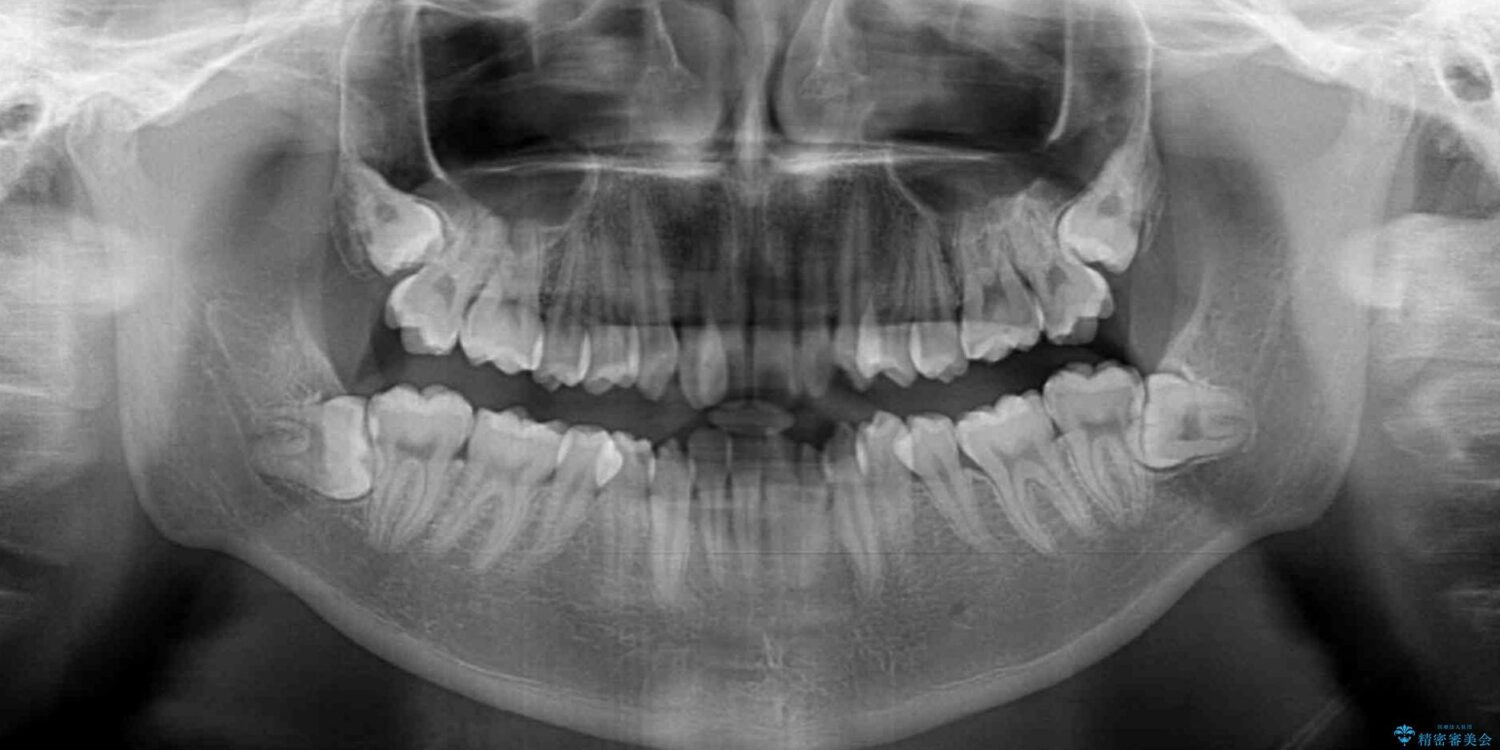

前歯のクロスバイトや八重歯の他に、左右最後臼歯のシザーズバイト(鋏状咬合)が認められました。

シザーズバイト改善のために補助装置を使用しながら、ワイヤー装置にて全体の歯列を整えることとしました。

シザーズバイトは強く咬合する奥歯を移動させるため、多くの場合においてワイヤー矯正の装置のみでは改善が困難となります。

奥歯の咬み合わせ改善は治療初期からしっかりとアプローチする必要があるため、補助装置を積極的に利用します。